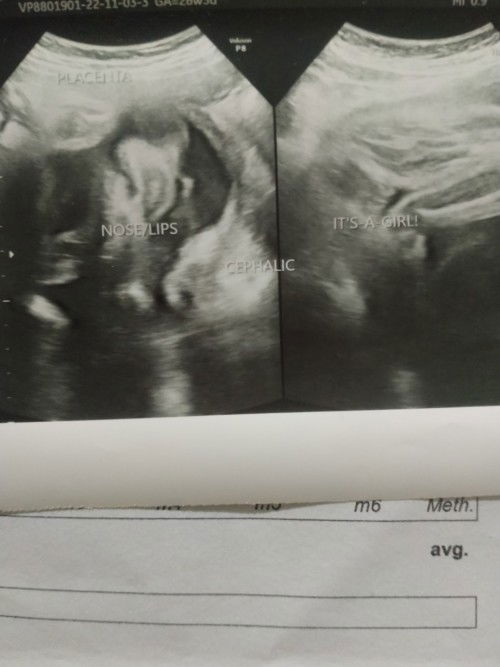

Sino ba dito marunong tumingin ng utz, okay lng po ba nose and lips ng baby ko?

nagpa ultrasound ako kanina, tpos ang bilis ni doc nag tanong2 naman ako kung lng bby ko sabi nia okay lng daw, baby girl daw si baby # firsttimemom #teamjanuary4

ung kmay ng baby tignan mo mi.. nka close fist siya near eye. ung nose halata nmn pero ung lips mlabo pero kita nmn na nka smile sa noo lng nklgay ung txt na nose/lips.

sis ganyan tlaga ang utz hehe hnd pa ganun kalinaw lalo na black and white lang. as long as sbi ni sonologist na ok si baby. kapag nagpa 4d scan ka makita mo tlaga face ni baby.

mii diko gets ung sa nose and lips , pero ung gender nya gets ko burger hehe girl nga walang palawit e hehe congrats mi ☺️❤️

If wala naman sinabi yung nag utz sayo mi na may prob, most probably okay naman si bb. Inonote naman nila yan if may mali

e note din po ba kung cleft palate yung baby?

Ang hitap kapag black and white pero kita ko nose and lips nya hihi 😍